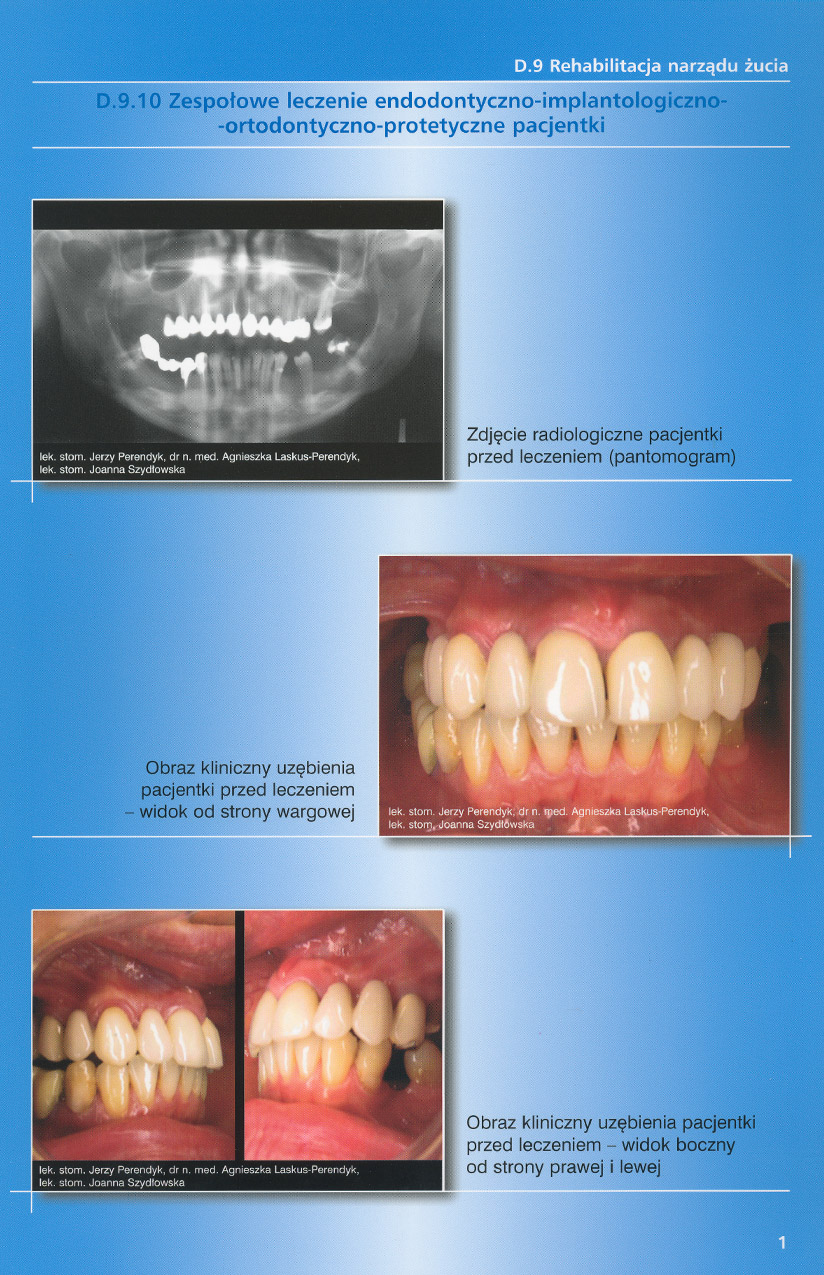

zobacz więcejGaleria przypadków klinicznych, obrazująca proces terapeutyczny od stanu wyjściowego aż do oddania ostatecznej pracy uzupełnienia brakującego uzębienia.